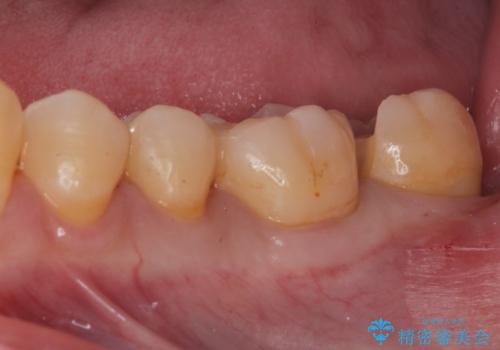

e-maxインレーによる治療

- 定期検診で来院してレントゲンを撮ったところ

歯と歯の間にう蝕ができていました。

拡大鏡下でう蝕を全て除去してe-maxインレーにて治療を行いました。